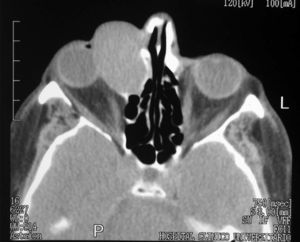

Se le realizó una TC orbitaria (figs. 1 y 2), sin administración de contraste intravenoso y se obtuvieron imágenes en los planos axial y coronal, con algoritmos de reconstrucción de partes blandas y de hueso. Se visualizaba la tumoración como una masa de partes blandas de densidad homogénea, morfología ovoidea, bordes bien definidos y contornos regulares, de 4 x 3 centímetros de diámetro anteroposterior y transversal respectivamente, localizada en el canto interno de la órbita derecha, que ocasionaba desplazamiento lateral del globo ocular y de la musculatura extrínseca ocular, con ensanchamiento del conducto lacrimonasal, que orientaba hacia un origen en el saco lacrimal. Se asociaba remodelación de las celdas etmoidales anteriores, sin evidenciarse signos de destrucción del hueso, ni afectación de estructuras vecinas.

Fig. 2.--Tomografía computarizada orbitaria, plano axial sin administración de contraste intravenoso. Corresponde a un plano más caudal que la figura 1, con algoritmo de reconstrucción de hueso, en la que se observa la masa descrita, adyacente a la pared medial de la órbita derecha, que produce remodelacón ósea de las celdas etmoidales anteriores vecinas, sin evidencia clara de destrucción del hueso. Conducto lacrimonasal izquierdo (flecha blanca).